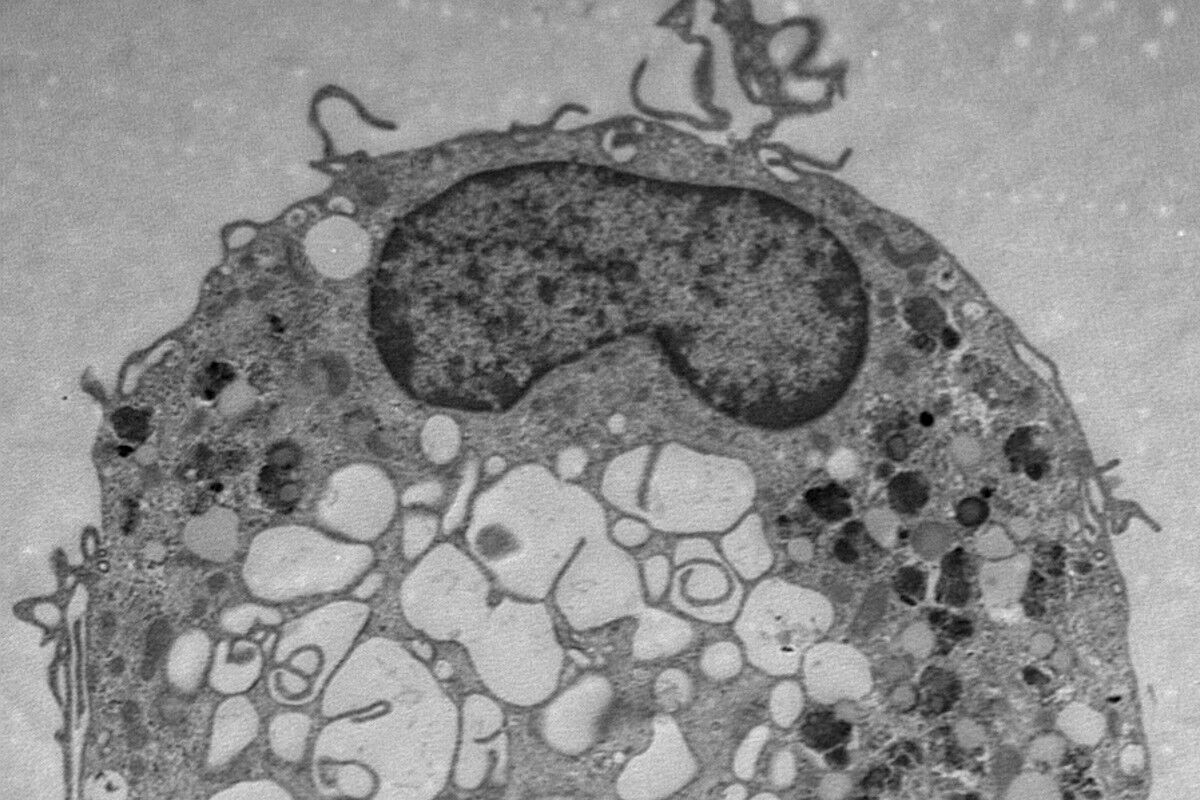

Les thèmes principaux d’EURIdoc sont l’hématopoïèse ainsi que le développement du système immunitaire, l’immunité innée et adaptative et des maladies immunitaires. Le projet porte également sur le problème immunologique le plus urgent de notre époque, le Covid-19, et prévoit, entre autres, de développer de nouvelles thérapies pour le SARS-CoV-2. La coopération allant au-delà du secteur universitaire avec quatre hôpitaux et dix partenaires industriels est à cet égard une base importante. Les doctorantes et doctorants auront ainsi la possibilité d’effectuer des séjours de recherche dans des entreprises pharmaceutiques de premier plan aussi bien que dans des entreprises de petite et moyenne taille.